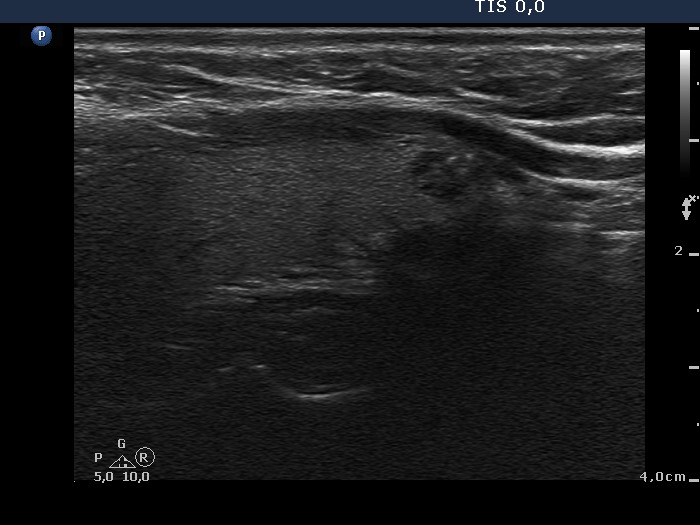

Case conp 031 (ultrasonographic picture 5)

Left lobe, another longitudinal scan.